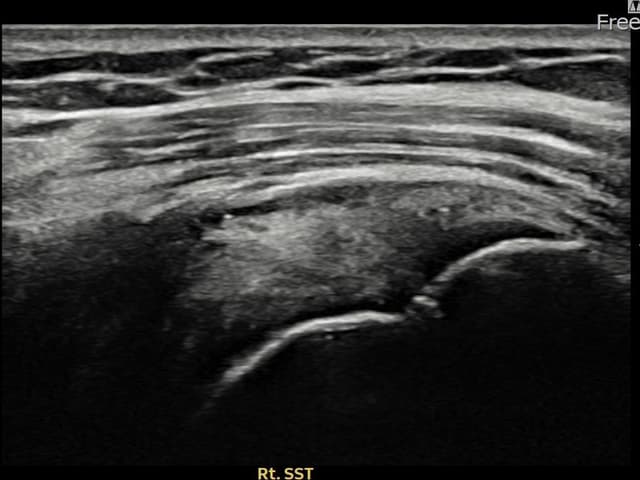

治療実績 — 超音波エビデンス

実際の患者様の施術前後の超音波画像。

手術なしで実現できる回復をご確認ください。

すべての超音波画像は患者様の同意を得て掲載しています。個人差があり、同一の結果を保証するものではありません。

[経過期間: 24.04.26~24.07.05]

[縫縮術] 超音波検査にて右 棘上筋腱 관절면측 광범위 部分断裂(16mm × 5mm (腱厚の約75%欠損))を確認。縫縮術施行後、腱の連続性が回復し、日常生活に復帰されました。